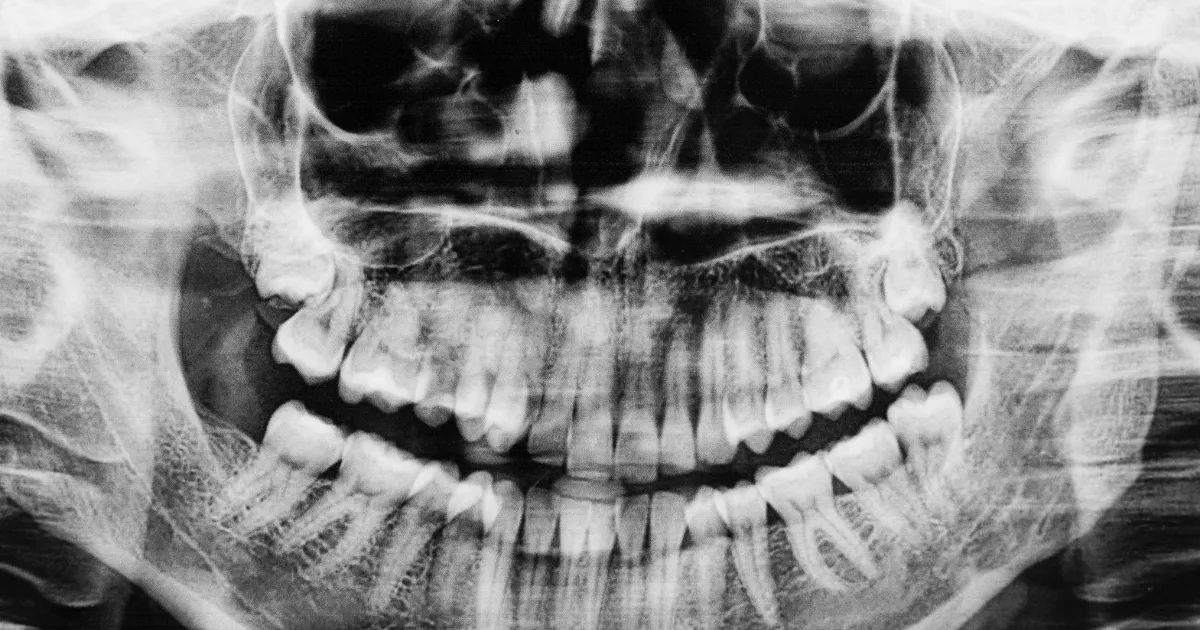

歯科ハミール高田88では、CT撮影や最新の3Dスキャナー「iTero」を導入しており、抜歯前の詳細な診断を行います。

これにより、歯の位置や形状、周囲の骨構造を正確に把握し、リスクを最小限に抑えた安全で確実な治療が可能です。

CTによる立体画像解析により、神経や血管の位置も明確にし、難易度の高い親知らずの抜歯にも対応しています。

この先端技術により、術後の合併症リスクも大幅に低減できます。